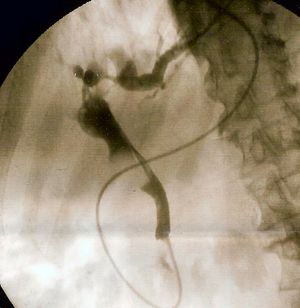

담도 폐쇄 진단을 위한 표준 검사는 여전히 내시경적 역행성 담관 췌장 조영술 (ERCP)이다. 이 검사는 내시경 (입을 통해 식도, 위를 지나 십이지장까지 삽입하는 관)을 이용하여 작은 도관(캐뉼라)을 담관 안으로 넣는 방식으로 진행된다. 이후 방사선 조영제를 주입하여 담관을 X선 영상에서 보이게 만든 뒤, X선 촬영을 통해 담도계의 구조를 확인한다. 내시경으로 팽대부를 직접 관찰하면 총담관에 박힌 담석 때문에 팽대부가 튀어나와 보이거나, 총담관 입구에서 고름이 흘러나오는 것을 명확히 볼 수도 있다. X선 영상(담관 조영술)에서는 담석이 담관 내에서 조영제가 채워지지 않는 그림자(음영 결손)로 나타난다. 진단 목적으로만 시행하는 경우, ERCP는 현재 MRCP로 대체되는 추세이다. ERCP는 진단 검사를 미룰 수 없는 위중한 환자에게 우선적으로 사용되거나, 담관염이 강력히 의심될 때 막힌 총담관의 내용물을 빼내는 치료(배액)를 위해 주로 시행된다.[1]

담관염의 확실한 치료법은 기반이 되는 담즙 폐색을 완화시키는 것이다.[33] 이는 일반적으로 환자가 안정되고 항생제에 약간의 호전을 보인 후 입원 후 24~48시간까지 연기되지만,[1] 적절한 치료에도 불구하고 지속적인 악화가 발생하거나,[1] 항생제가 감염 징후를 줄이는 데 효과가 없는 경우(15%의 경우 발생) 응급 상황으로 진행될 수 있다.[4][14]내시경적 역행성 담관 췌장 조영술(ERCP)은 담관의 막힌 것을 제거하는 가장 일반적인 방법이다. 이 시술은 내시경(광섬유 튜브를 위를 거쳐 십이지장으로 통과시키는 것)을 사용하여 파터 팽대부를 확인하고 담관에 작은 튜브를 삽입하는 과정을 포함한다. 일반적으로 오디 괄약근에 절개를 가하는 괄약근 절개술을 시행하여 담즙 흐름을 원활하게 하고, 총담관을 막고 있는 담석을 제거하기 위한 기구를 삽입할 수 있도록 한다. 또는 이와 함께 풍선으로 총담관 구멍을 확장할 수도 있다.[15] 담석은 직접 흡입하거나, 담관을 훑어 담석을 십이지장으로 끌어내는 풍선이나 바스켓 같은 다양한 기구를 사용하여 제거할 수 있다. 큰 담석으로 인한 폐쇄는 제거 전에 기계적 쇄석기를 사용하여 담석을 부수는 과정이 필요할 수 있다.[16] ERCP로 제거하거나 기계적으로 부술 수 없을 정도로 큰 폐쇄 담석은 체외 충격파 쇄석술로 관리할 수 있는데, 이는 신체 외부에서 음향 충격파를 가해 담석을 파괴하는 기술이다.[17] 매우 큰 폐쇄 담석을 제거하는 또 다른 방법은 전기 수압 쇄석술이다. 이 방법은 담관경이라는 작은 내시경을 ERCP로 삽입하여 담석을 직접 보면서 프로브를 이용해 전기로 충격파를 발생시켜 폐쇄 담석을 부순다.[18] 드물게는 복강경 수술을 통해 총담관을 직접 탐색하여 담석을 제거하는 담관 절개술이 필요할 수도 있다.[19]